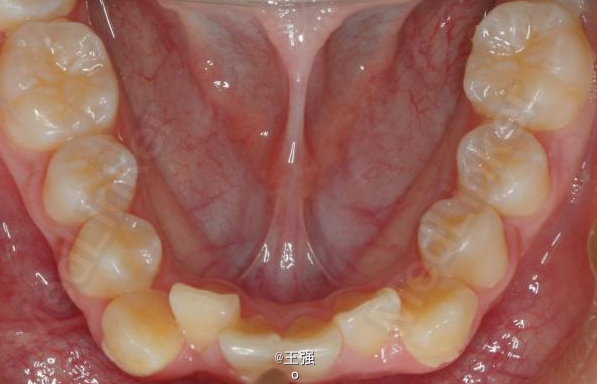

在临床上,我们常常会遇到亚类病例,对于亚类病例,有时需要不对称拔牙,常见的不对称拔牙方法有:上颌对称,下颌数目对称但是位置不对称。还有上颌对称,但是下颌数目不对称。其目的就是为了取得尽可能理想的尖窝对应咬合关系 该病例右侧是中性关系,左侧是中性偏远中关系,上颌中线正,下颌中线左偏约1mm。左侧磨牙关系距离中性关系约差2mm左右。如果采用对称性拔除下颌左右四,我们面临的问题是,一、如何保证矫治后上下中线一致,二、如何保证左侧磨牙关系矫治后为中性关系。治疗过程中势必会用到不对称牵引。我个人认为除非是功能性的因素,矫治过程中最好不要用不对称牵引。 关于中线和磨牙关系的问题,我认为应在矫治计划制定时就应考虑到,而不是等到矫治第三阶段所谓精细调整阶段再来解决。事实上到了这个阶段采用了不对称的牵引,即使暂时取得了中线对齐的矫治目的也是不稳定的。 这个病例,用了不对称的拔牙,右下拔四,左下拔五。下颌牙齿在漂移的过程中(几乎没有外来力量),下前牙自然就会向右比向左多漂移一些,中线在下颌还没有开始矫治时就对齐了,左下六因没有五的存在,自然就向近中多漂移一些,和上颌六形成中性关系。接下来的矫治就会非常简单,而结果自然也非常稳定。